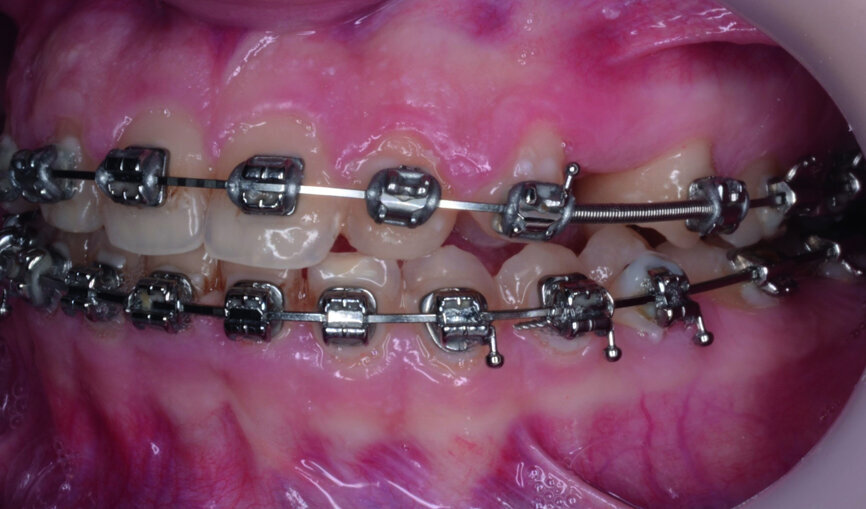

- Upper bracket placement (Fig. 22): level and align the gingival margins, and correct the torque on the upper canines who will substitute the lateral incisors.

- Implants space opening: substitute laterals with canines (Figs. 23–25) and substitute canines with first premolars (Figs. 26–28).